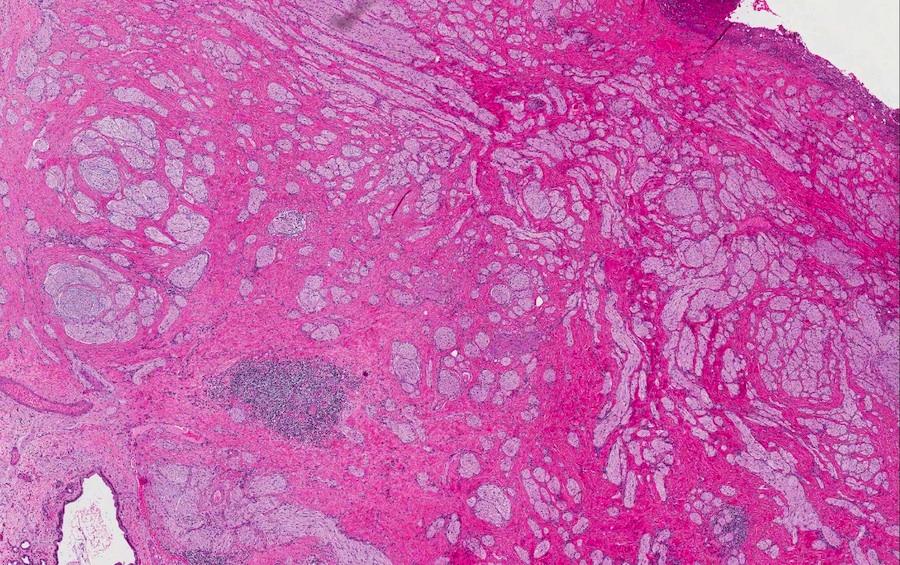

Microscopic images:

Both cases showed disorganized and thickened nerve bundles composed of spindle shaped cells, without atypia. Case A also showed a focal foreign body type giant cell reaction adjacent to the disorganized nerve bundles and a strongly immunoreactive S100 stain.

Histology typically shows hyperplastic nerve bundles, positive for S100.

Microscopic images:

Both cases showed disorganized and thickened nerve bundles composed of spindle shaped cells, without atypia. Case A also showed a focal foreign body type giant cell reaction adjacent to the disorganized nerve bundles and a strongly immunoreactive S100 stain.

Histology typically shows hyperplastic nerve bundles, positive for S100.